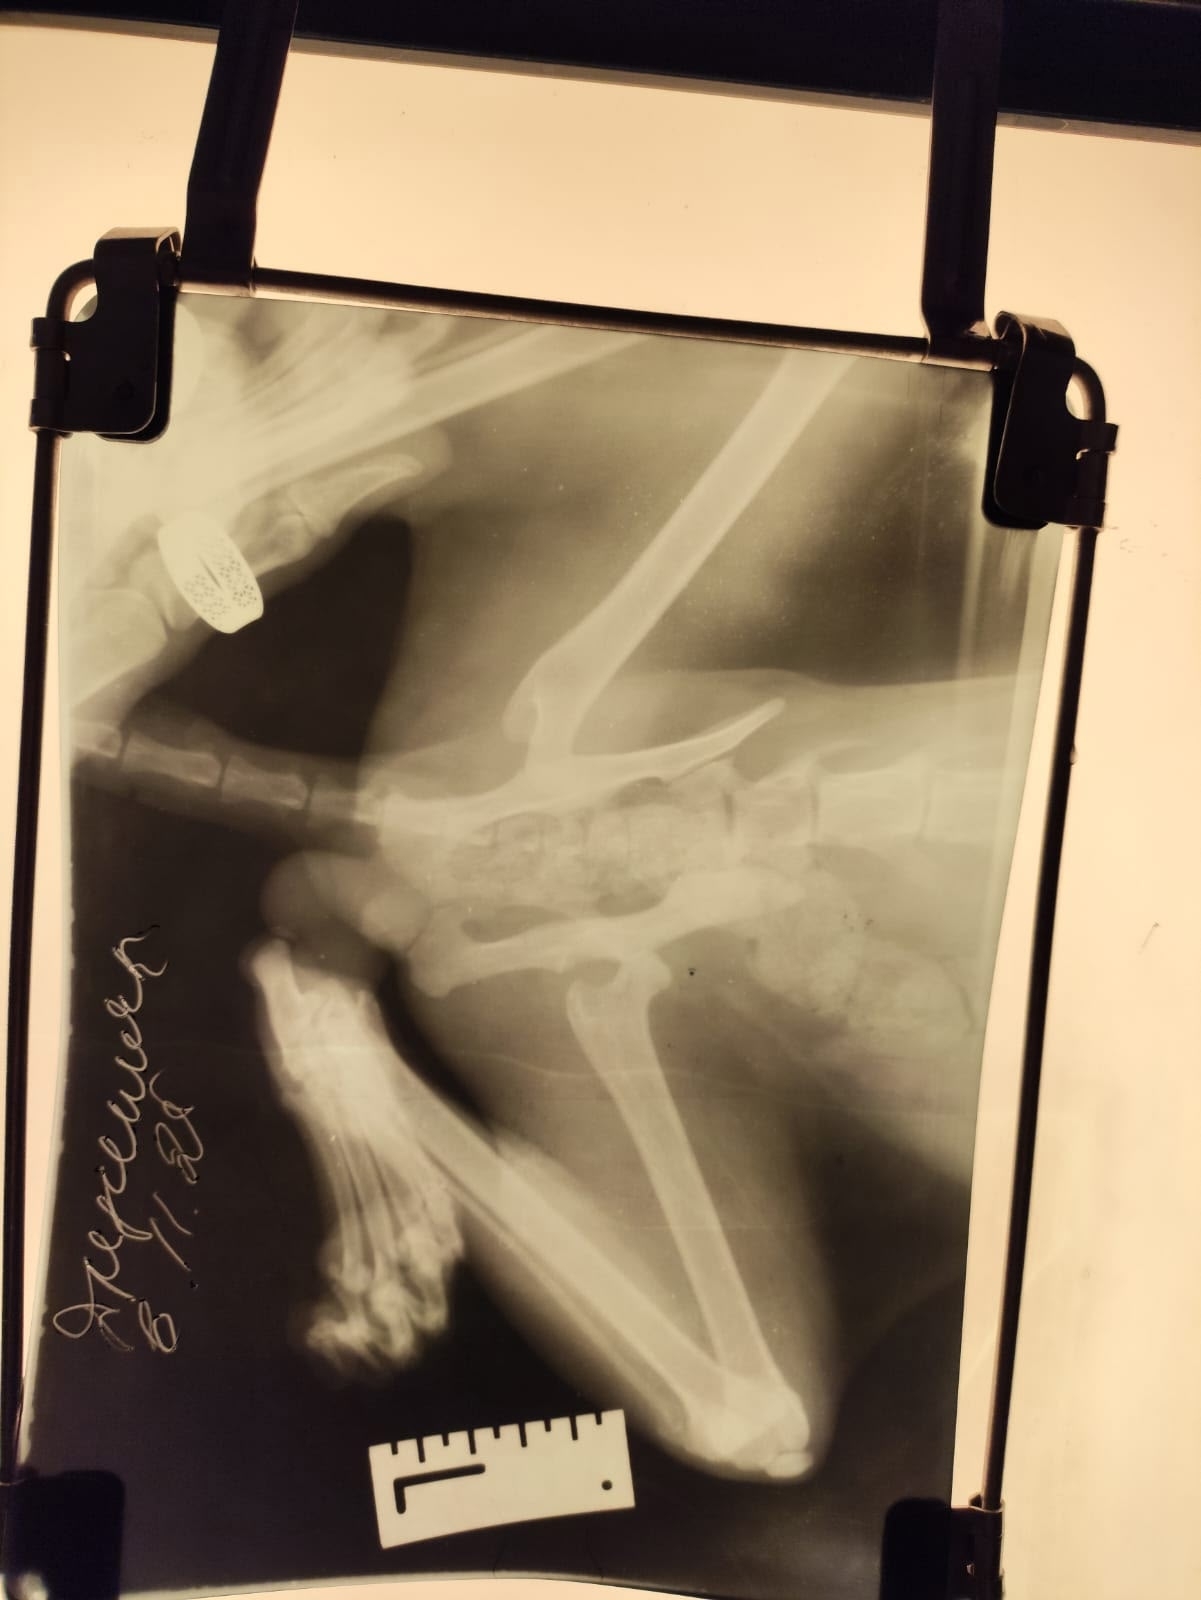

Помогите Персику спасти лапку🙏🙏🙏

Был найден мною на обочине проспекта строителей, сбила машина. Кот пытался встать что бы отбиться от собаки, я очень во время спас его.

Повезло что поврежденная ножка может быть спасена. Кот кушает и пьет.

Что бы спасти ножку требуется как можно быстрее провести операцию на тазобедренном суставе.